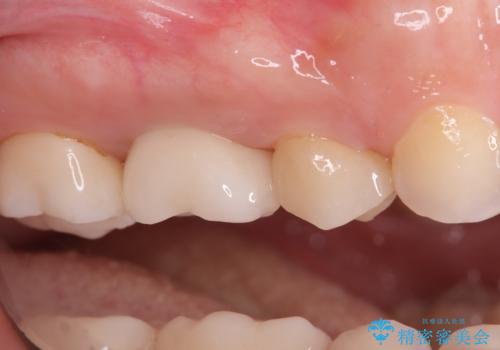

今回の治療では、まず原因となっていた奥歯を慎重に抜歯し、その直後にインプラントを埋入しました。この抜歯即時埋入により、抜歯からインプラント埋入までの期間を省き、骨の吸収を最小限に抑えられました。治療後は痛みや腫れも少なく、患者様は快適に過ごしていただけました。最終的に、わずか3ヶ月でセラミッククラウンを装着。機能性と審美性を兼ね備えた新しい歯により、長年の痛みが解消され、快適な食生活を取り戻していただけました。